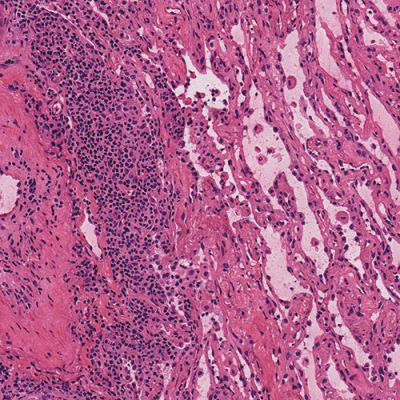

High Quality Results

Pathologists rely heavily on the frozen section technique for intra-operative consultation when the surgeon requires a rapid diagnosis or immediate feedback regarding surgical margins. Frozen sections offer a short turnaround time (15-20 minutes) but usually have the disadvantage of lower diagnostic quality than paraffin sections due to cryoembedding artifacts and variability in staining protocols.

Milestone offers a new approach to overcome these limitations by combining the artifact-free freezing process of PrestoCHILL with the superior processing and staining capabilities of PRESTO PRO.

The advantage of PRESTO PRO is that it provides a standardized and reproducible process that is capable of both efficient processing and staining protocols. This results in improved morphology of the analyzed specimens and maintains a high standard of result quality.